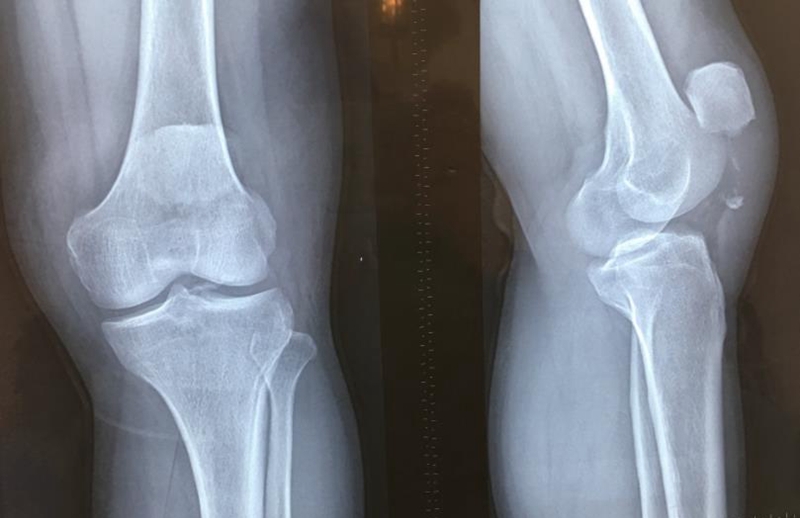

吕某,男,32岁,左髌骨下极撕脱骨折7天,2020年4月16行“双套固定法”手术。

术前资料

术后影像学